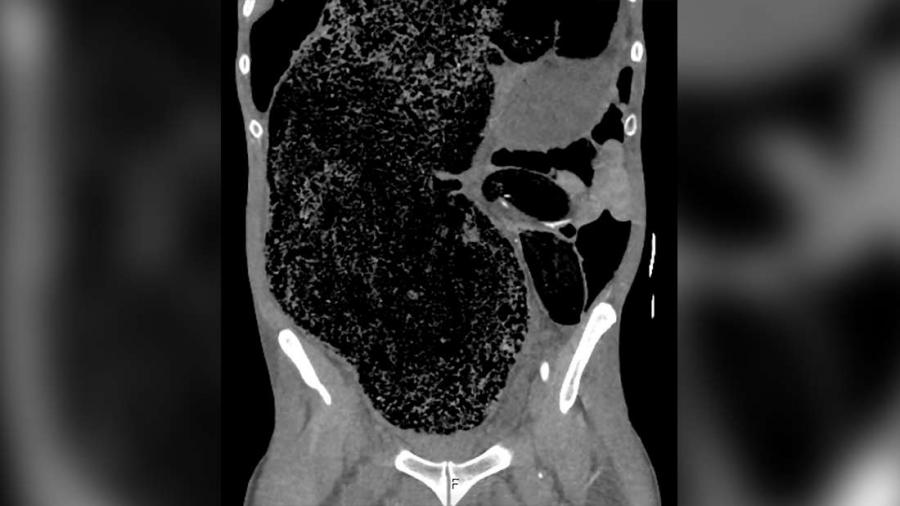

След преглед на ректума лекарите установяват, че мъжът е имал сериозен запек. Скенер на коремната кухина показва, че става дума за потенциално опасен за живота Синдром на коремното отделение (повишено налягане в коремната кухина).

Изпражненията са се струпали до такава степен, че са разширили голямото черво и са оказали силен натиск върху неговата дясна вътрешна срамна артерия. Това налягане е предизвикало болката в крака и съответно е довела до парализата.

Мястото, където фекалиите са оказали натиск върху артерията. Източник: BMJ Case Reports.